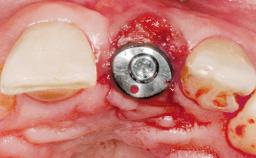

Late Placement of an Implant in a Maxillary Left Central Incisor Site

# of Implants 1

Type of Implants Two-Piece

Attachment Two-Piece

Loading Protocol Conventional or early